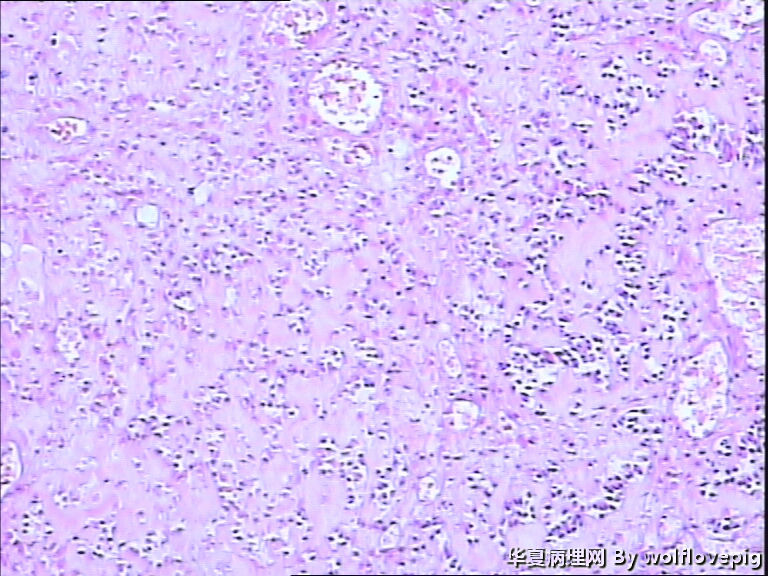

求助!肌瘤变性?

图2